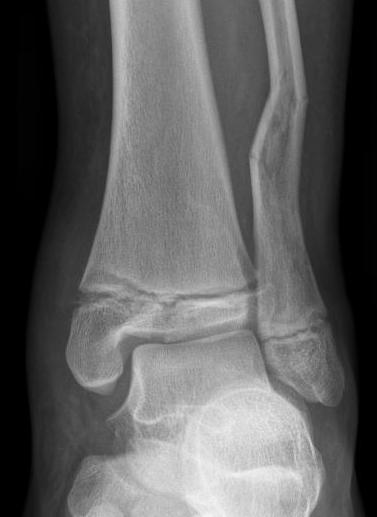

| SH I distal tibia / fibula | SH II distal tibia | SH III medial malleolus |

![]() |

| Low risk growth arrest | 40% risk growth arrest | 30% risk physeal bar |